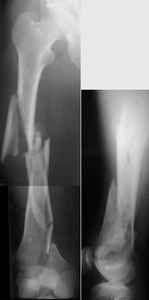

KEMMD> B. Fixation loosening: distal cutting of the nail, non-unions do happen

KEMMD> (cases attached).